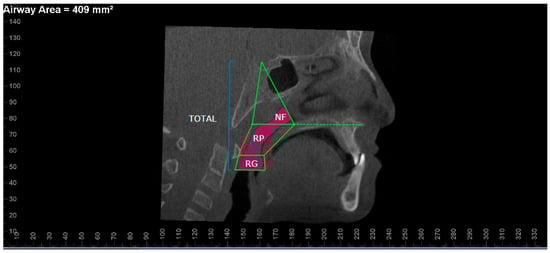

2. Materials and Methods